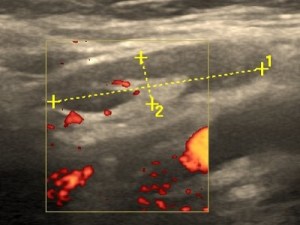

Narządy jamy brzusznej

Uwzględnia narządy: nadbrzusza, śródbrzusza i podbrzusza – choroby wątroby, nerek, śledziony, prostaty i inne zlokalizowane w jamie brzusznej. Do badania trzeba być około 4-6godz. na czczo i z umiarkowanie wypełnionym pęcherzem moczowym.

Kamień w nerce.